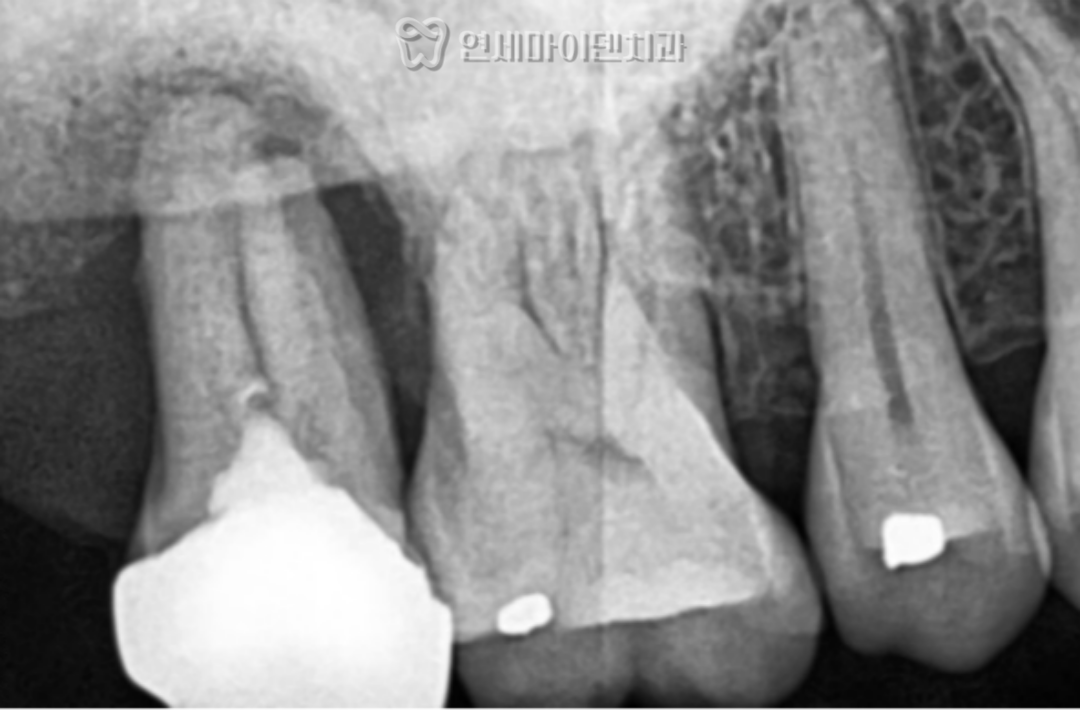

치료 전 상태: 뼈가 거의 없는 상황

이번 환자분은

오른쪽 위 어금니는 심하게 흔들리는 상태였고

아래 왼쪽 어금니는 발치 후 오래 방치되었습니다.

CT를 확인해보니

뼈가 거의 남아 있지 않았고,

손으로도 발치가 가능할 정도였습니다.

이 상태를 오래 두면

주변 치아까지 손상될 수 있습니다.

4년 경과: 결과는?

이번 케이스는

4년이 지난 현재까지

✔ 임플란트 안정적 유지

✔ 주변 치아 뼈 레벨 유지

✔ 정기 관리 지속